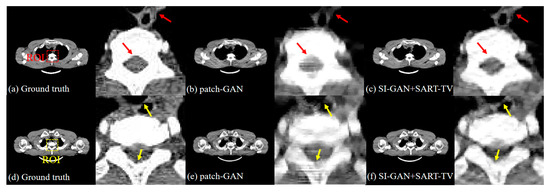

| PSNR | RMSE | NMAD | SSIM | ||

|---|---|---|---|---|---|

| Slice 1 | FBP | 13.6388 | 2.52 × 10−3 | 0.9820 | 0.9564 |

| SART-TV | 21.9823 | 1.02 × 10−3 | 0.2843 | 0.9939 | |

| patch-GAN | 29.6305 | 4.04 × 10−4 | 0.1002 | 0.9983 | |

| SI-GAN + FBP | 24.4512 | 9.55 × 10−4 | 0.3874 | 0.9929 | |

| SI-GAN + SART-TV | 35.3856 | 2.25 × 10−4 | 0.0504 | 0.9989 | |

| Slice 2 | FBP | 11.4794 | 2.44 × 10−3 | 0.9954 | 0.9589 |

| SART-TV | 23.5963 | 8.71 × 10−4 | 0.2603 | 0.9953 | |

| patch-GAN | 29.8019 | 4.01 × 10−4 | 0.1162 | 0.9982 | |

| SI-GAN + FBP | 24.4064 | 9.07 × 10−4 | 0.3882 | 0.9935 | |

| SI-GAN + SART-TV | 35.1920 | 2.41 × 10−4 | 0.0714 | 0.9987 |